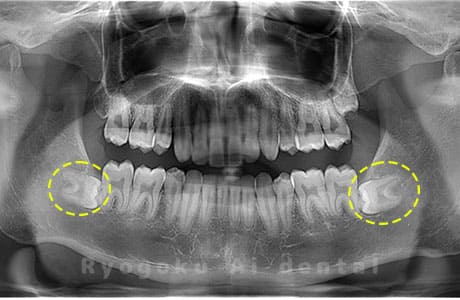

Case02

-

- 原因

- 下顎の水平埋伏智歯

- 治療内容

- 下顎の水平埋伏智歯を抜歯

<リスク・副作用>

手術後は痛み、腫れ、痺れなどの副作用が生じる場合があります。